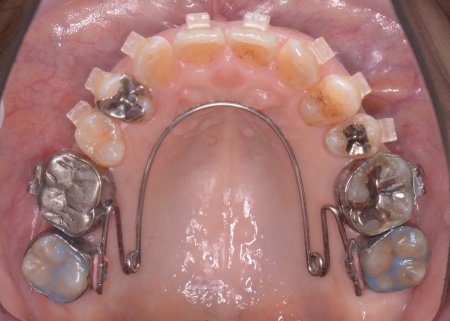

②①と並行して上下歯列にワイヤー矯正のマルチブラケット装置を装着し、歯並びと噛み合わせを整える。

③矯正治療と並行して左下奥歯を抜歯し、インプラント治療を行う。

インプラントを支えるための骨の量が十分でないため、人工材料を用いて骨を再生させる骨造成(GBR)を併用しながらインプラントを埋入する。

インプラントがしっかりと骨に定着したことを確認してから、人工歯を取り付ける。